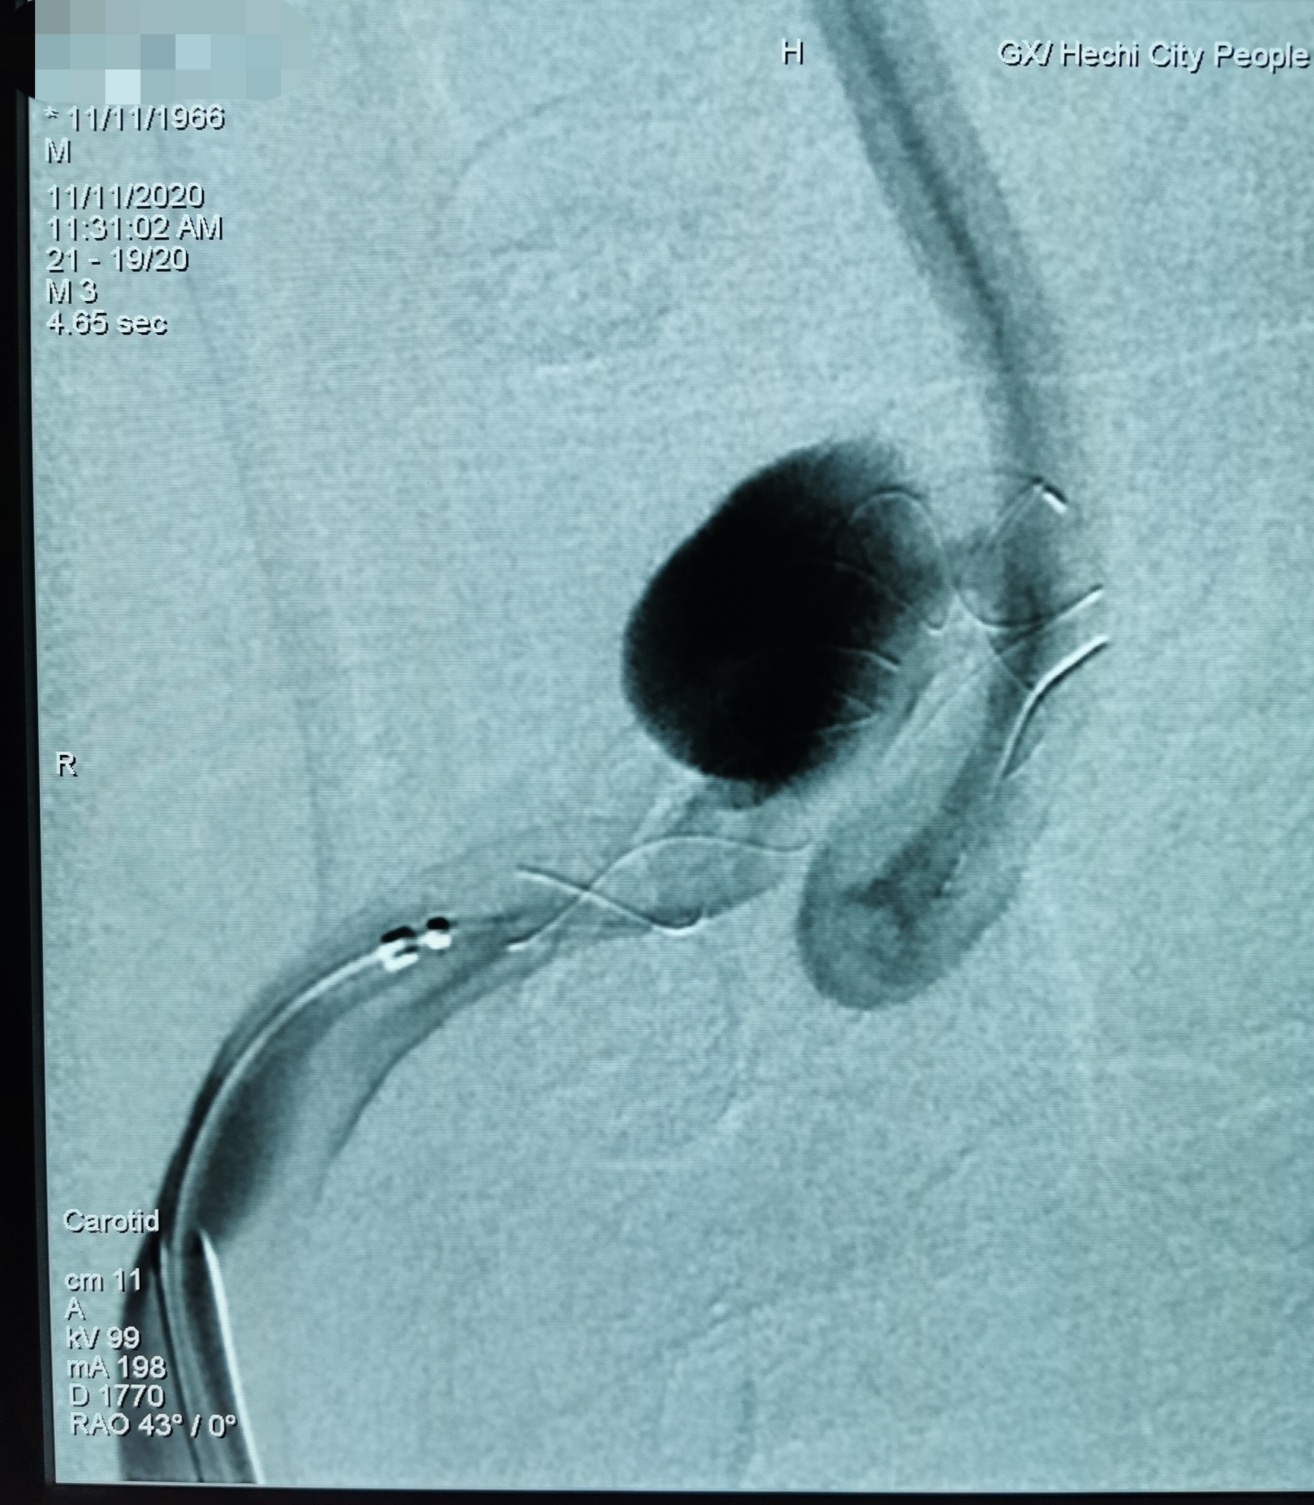

DSA检查发现右侧颈内动脉大型动脉瘤

经过细致的术前准备后,班先生被送入介入导管室进行手术。术中发现班先生右侧颈内动脉一夹层动脉瘤,长14.4mm×高6.2mm,瘤颈宽10.8mm,合并左侧大脑中动脉重度狭窄。韦仕荣主任经过精细操作在患者右侧颈内动脉夹层动脉瘤处置入Tubridge血管重建装置,精确到位,即刻造影可见病变血管的血流形态明显改善。之后在左侧大脑中动脉重度狭窄处予球囊扩张成形术,造影显示血管狭窄明显改善,一次手术解决了两处重大的脑血管病变,手术过程顺利,且无并发症发生。次日班先生即可正常活动,恢复良好,术后第5天即康复出院。